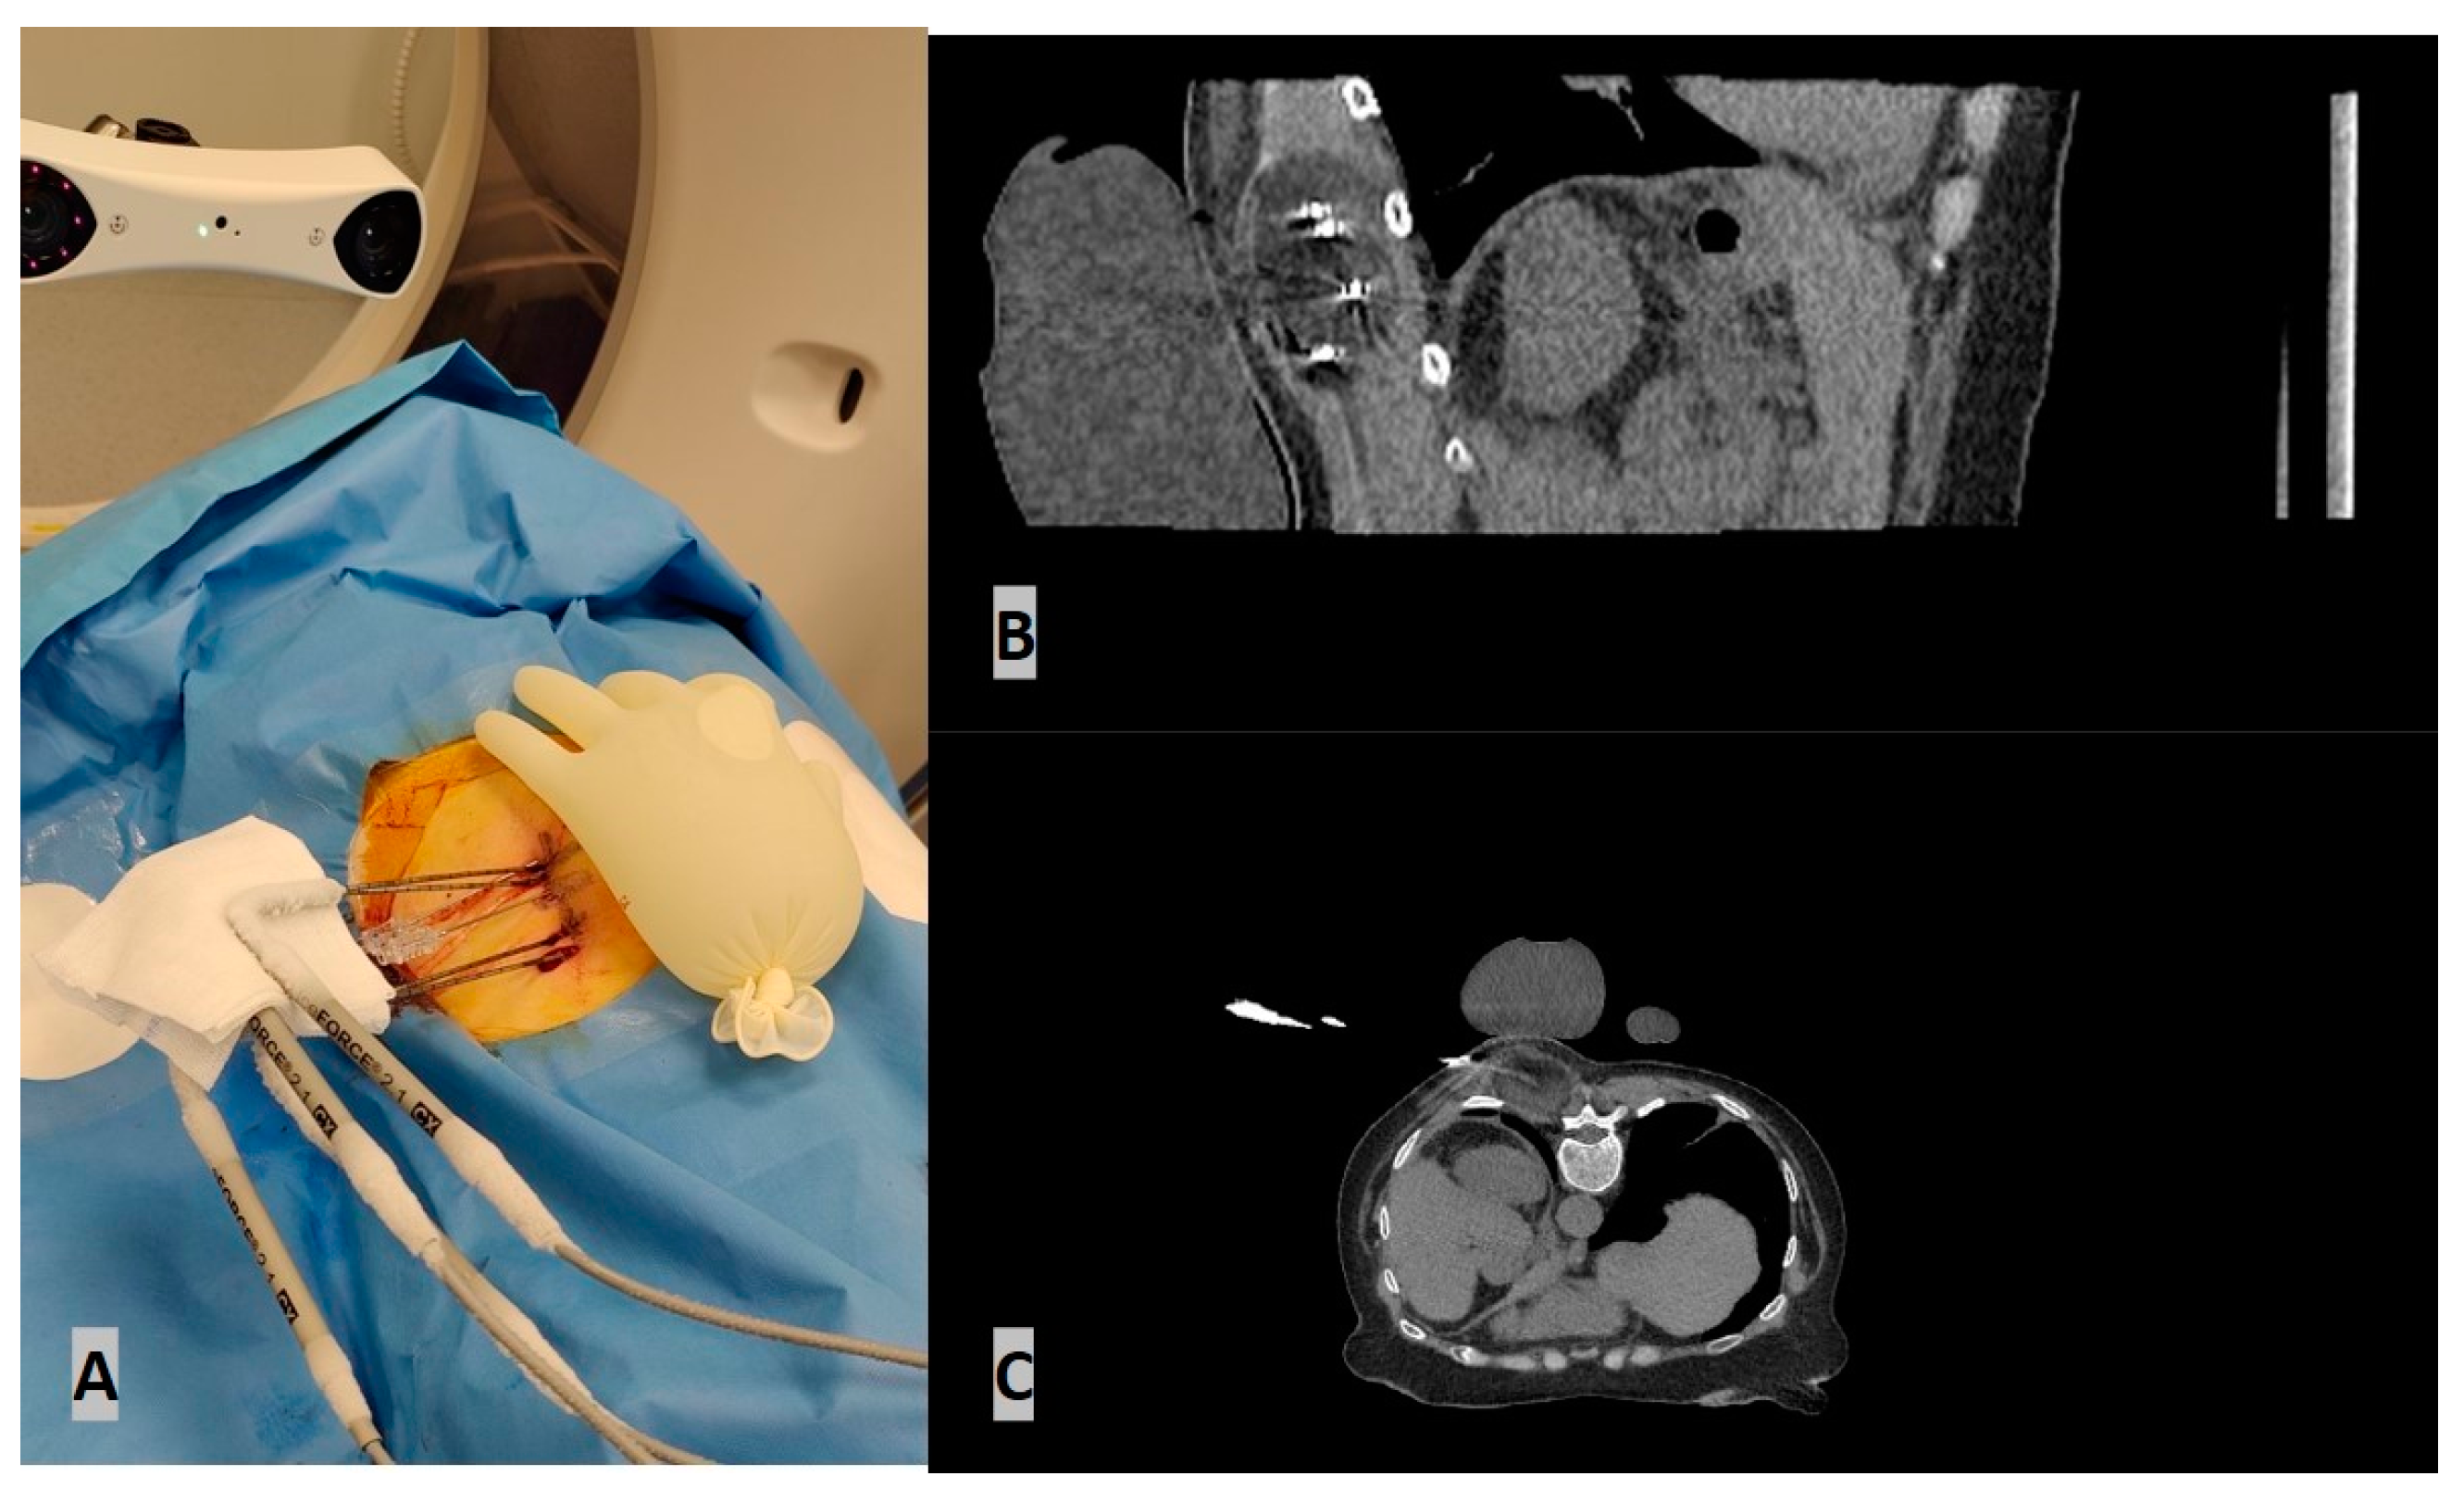

- Bale, R.; Widmann, G. Navigated CT-guided interventions. Minim. Invasive Ther. Allied Technol. 2007, 16, 196–204. [Google Scholar] [CrossRef] [PubMed]

- Bale, R.; Widmann, G.; Stoffner, D.R. Stereotaxy: Breaking the limits of current radiofrequency ablation techniques. Eur. J. Radiol. 2010, 75, 32–36. [Google Scholar] [CrossRef] [PubMed]

- Bale, R.; Laimer, G.; Schullian, P.; Alzaga, A. Stereotactic ablation: A game changer? J. Med. Imaging. Radiat. Oncol. 2023. [Google Scholar] [CrossRef] [PubMed]

- Schullian, P.; Laimer, G.; Johnston, E.; Putzer, D.; Eberle, G.; Scharll, Y.; Widmann, G.; Kolbitsch, C.; Bale, R. Technical efficacy and local recurrence after stereotactic radiofrequency ablation of 2653 liver tumors: A 15-year single-center experience with evaluation of prognostic factors. Int. J. Hyperth. 2022, 39, 421–430. [Google Scholar] [CrossRef]

- de Baere, T.; Roux, C.; Deschamps, F.; Tselikas, L.; Guiu, B. Evaluation of a New CT-Guided Robotic System for Percutaneous Needle Insertion for Thermal Ablation of Liver Tumors: A Prospective Pilot Study. Cardiovasc. Intervent Radiol. 2022, 45, 1701–1709. [Google Scholar] [CrossRef]